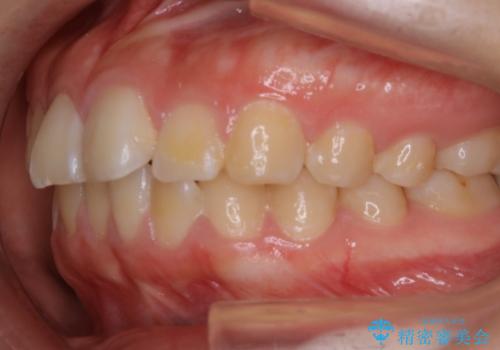

【非抜歯】ガタつきと歯軸を正して長持ちする歯へ

- 歯のガタつきと噛み合わせの改善を主訴に来院されました。

非抜歯で、少量の奥歯の移動と歯列の拡大・IPRを駆使して主訴を改善するための治療計画を立案しました。

マウスピースとマイクロインプラントを組み合わせることで、抜歯をしなくても歯並びを治すためのスペースを作ることができます。奥歯から順に移動させていくので前歯に変化が出るまでには時間がかかりますが、どの分健康な歯を抜歯することなく理想的な歯並びを手に入れることができます。